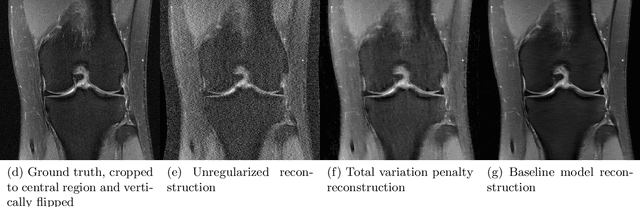

Abstract:Accelerating Magnetic Resonance Imaging (MRI) by taking fewer measurements has the potential to reduce medical costs, minimize stress to patients and make MRI possible in applications where it is currently prohibitively slow or expensive. We introduce the fastMRI dataset, a large-scale collection of both raw MR measurements and clinical MR images, that can be used for training and evaluation of machine-learning approaches to MR image reconstruction. By introducing standardized evaluation criteria and a freely-accessible dataset, our goal is to help the community make rapid advances in the state of the art for MR image reconstruction. We also provide a self-contained introduction to MRI for machine learning researchers with no medical imaging background.